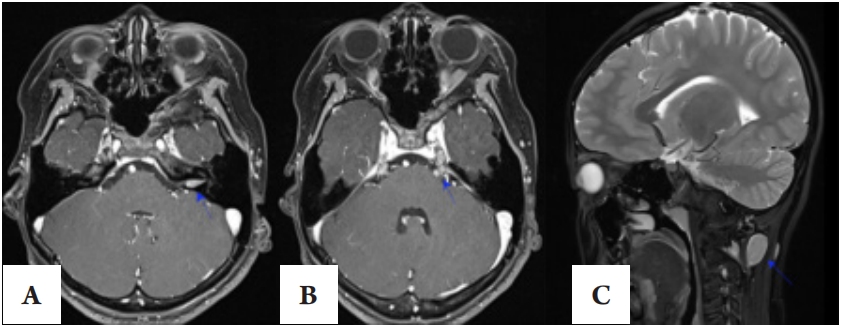

4例患者均伴有视力下降,最佳矫正视力从手动到0.8。3例患者行眼底光学相干断层成像(optical coherence tomography, OCT)检查(图1)显示视网膜错构瘤2例,视网膜前膜2例,视盘隆起2例,视网膜神经纤维层和节细胞层变薄1例。其他表现包括麻痹性斜视1例,复视1例,白内障1例,球后段视神经增粗1例,眼眶肿瘤1例(见表2)。

图1 OCT图像

Figure 1 Optical coherent tomography of the fundus

(B) 视网膜前膜,右眼黄斑中心凹颞侧神经上皮层前见中低信号膜状物。

(C) 视网膜前膜伴视网膜错构瘤,左眼黄斑中心凹颞上方神经上皮层增厚,各层分界不清,表面信号粗糙,可见火焰状膜状物附着。

(A) Anterior retinal membrane with dystoma. The nerve epithelial of the concave nasal in the center of the macular of the right eye showed thickening, the boundaries of each layer were unclear, and the surface signal was rough.

(B) Anterior retinal membrane. Medium and low signal membranes in front of the concave temporal nerve epithelium in the center of the macula of the right eye.

(C) Anterior retinal membrane with dystoma. The nerve epithelial layer above the concave temporal in the center of the macular of the left eye showed thickening, the boundaries of each layer were unclear, and the surface signal was rough, which could be seen as a flame-like membrane attachment.